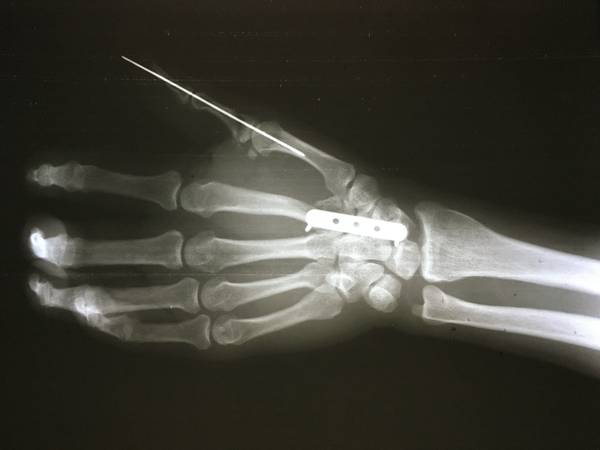

[断指再植] 一例断指断掌断腕?

整体还行,没有缺损,都是直接吻合没有移植